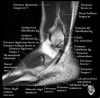

- Coronal section

The coronal oblique T1 sequence follows the tendons of the ankle around the malleolar turns and also evaluates the medial ankle ligaments.

The coronal oblique PD fat suppressed sequence follows the tendons of the ankle around the malleolar turns and is particularly important in evaluation of the Posterior tibialis tendon.

Bone and marrow

Talar dome

Deltoid ligament

Tendons in arch

Plantar fascia

Troubleshoot ligaments